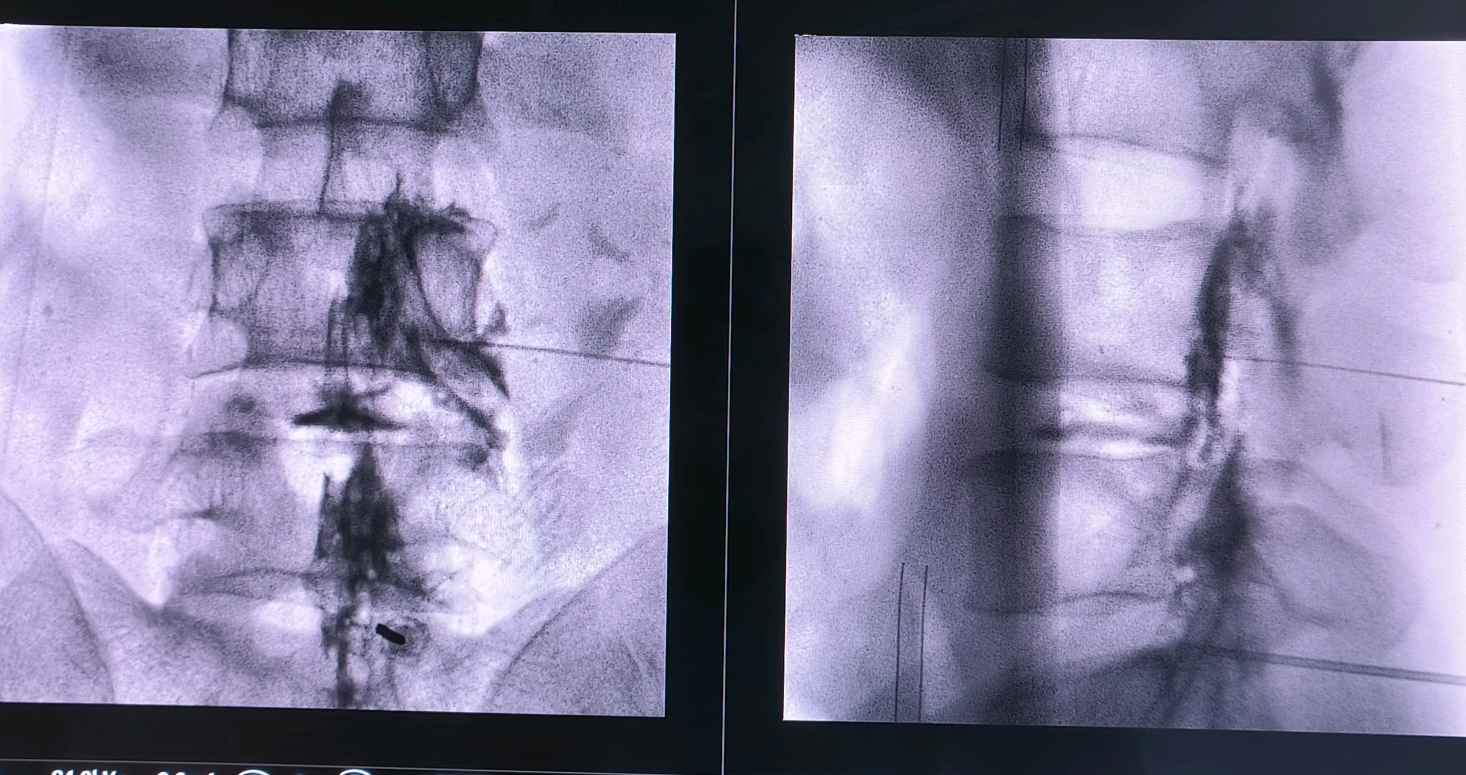

有,胶原酶技术是个古老而又新兴的技术,胶原酶可以水解突出的椎间盘,变成水和氨基酸,更绿色,更微创,无痛苦,可以说是一根针一个针眼解决椎间盘突出

问题,不开刀,临床疗效不差于开放手术!